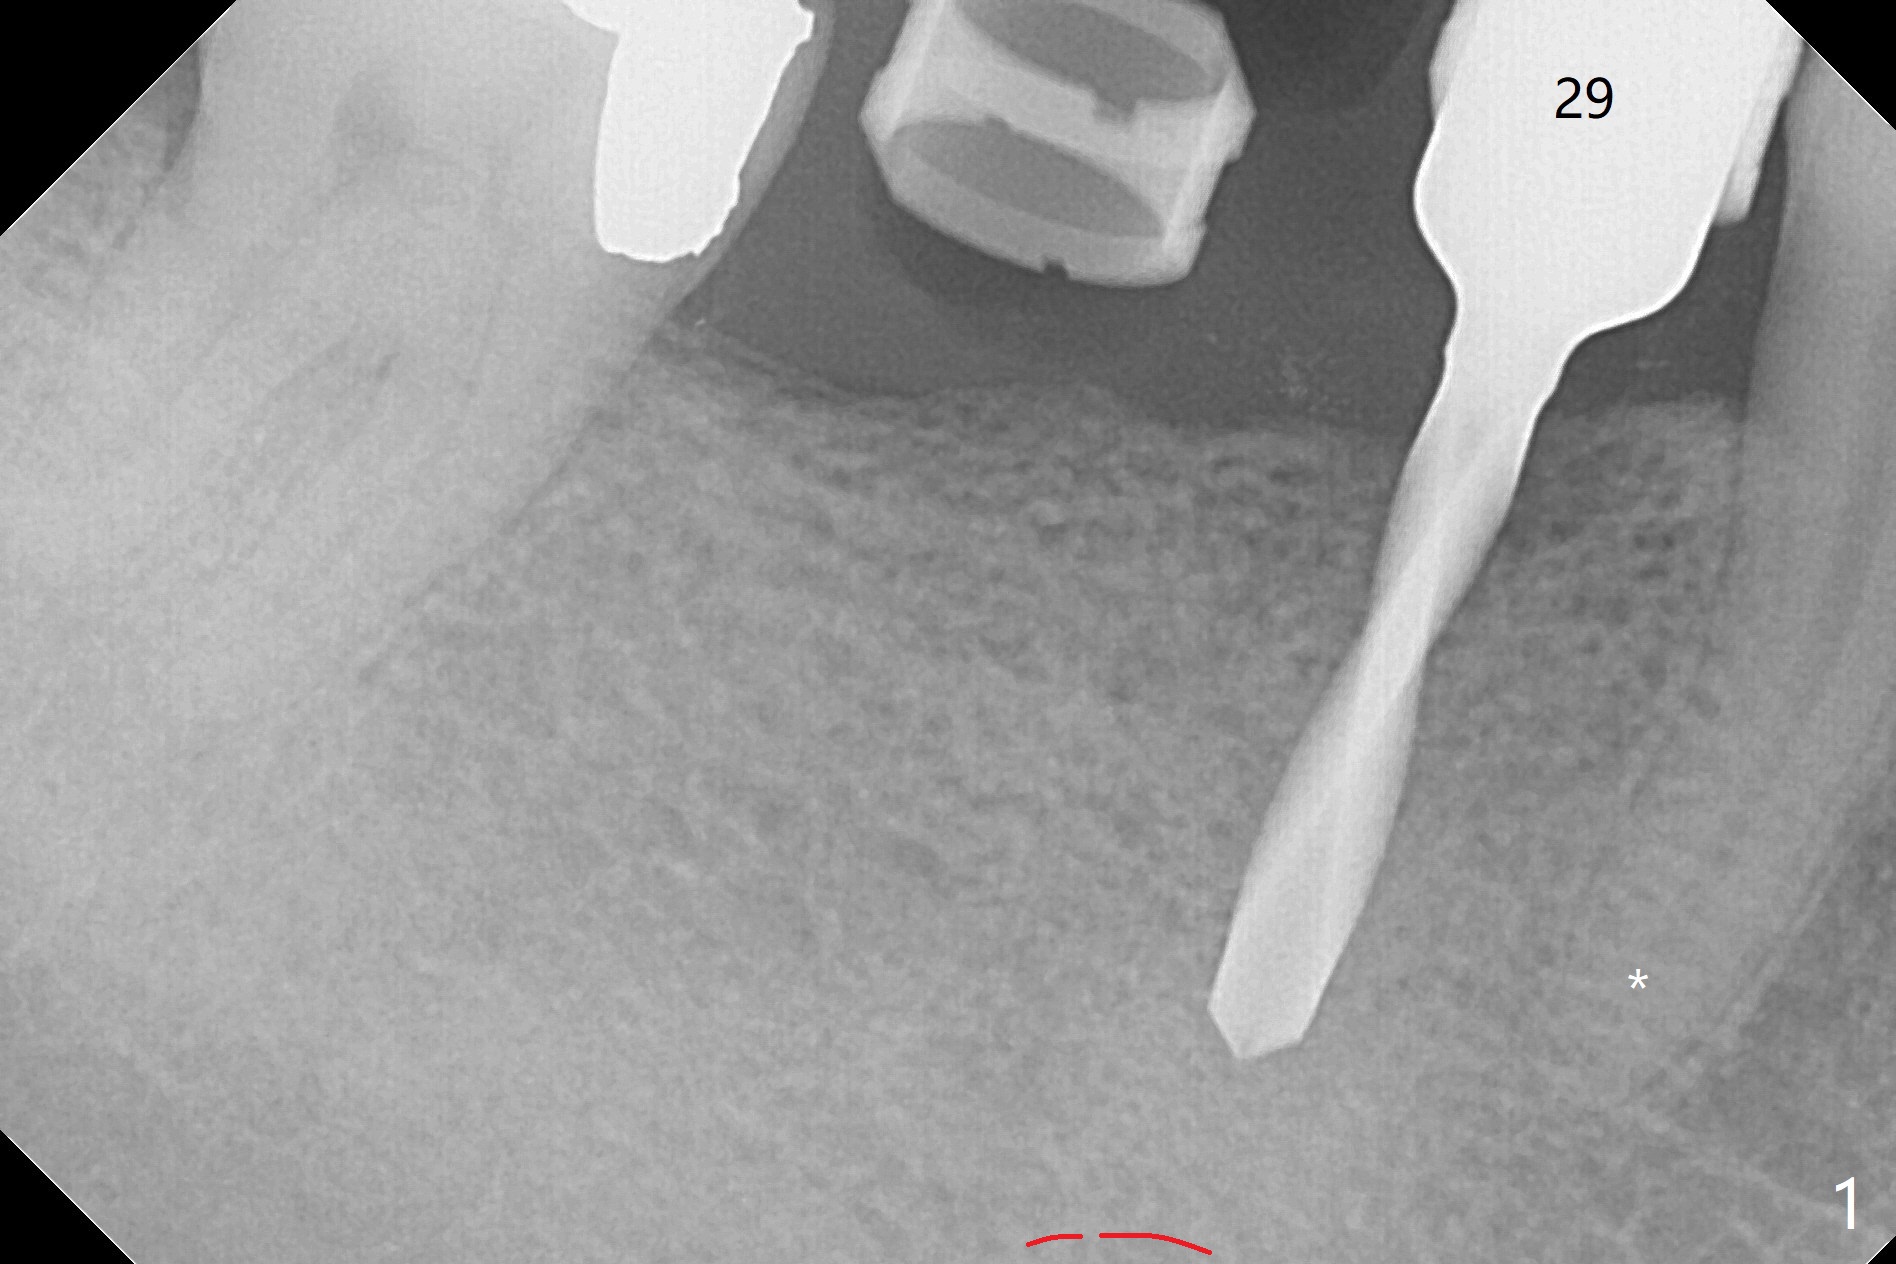

PA is taken after a 2.2 mm drill reaches depth of 11.5 mm with 10.5 mm offset at #29 to confirm that the curved apex of the neighboring tooth is not violated (Fig1 * (red line: Mental Loop)). The rest of the procedure is smooth except that the abutment at #29 is later changed to 4.5x4(4) mm (Fig.2,3 (red dashed line: Mental Loop)). The latter is easier for immediate splinted provisional and also has clearance from the crestal bone (Fig.5 *). Bone resorption seems to be minimal 4 months postop (Fig.4). The change in the abutment in cuff length (from 5.7x4.5(3) to (4) mm) at #30 eliminates the gag between the implant and abutment (Fig.4 <, as compared to Fig.5) before impression.